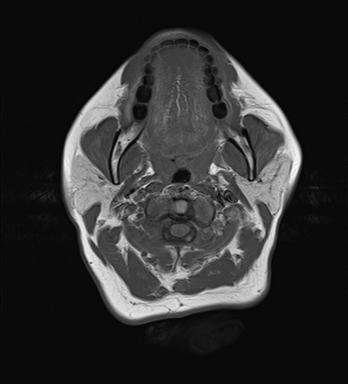

Thoát vị đỉnh xương đá (Petrous apex cephalocele)